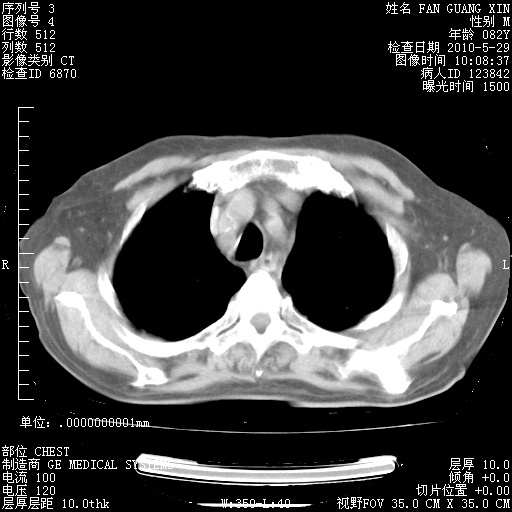

治疗3周后的肺部CT纵隔窗

从胸部影像学来看,的确有好转。至于目前为何发热不甚清楚?除了发热还有其他症状如有无喀痰,痰呈丝状吗?等等。尽量搜寻有无致发热其它可能原因?真菌?其它?如果的确无其他致发热的原因,考虑将甲强龙调至60-80mg bid/日。免疫全套基本无异常,考虑多系特发性肺间质纤维化